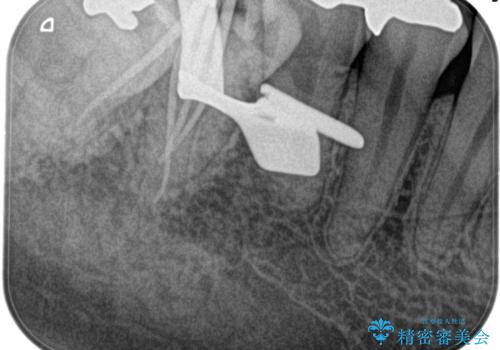

【根管治療】昨日から眠れないぐらい歯が痛い

検査の結果、不可逆性歯髄炎の診断とし根管治療を行なっております。

- 精密根管治療(イニシャルケース,大臼歯):122,000円、ファイバーコア:22,000円費用は治療当時の料金となります

根管治療した歯は、クラウン修復が必要です。